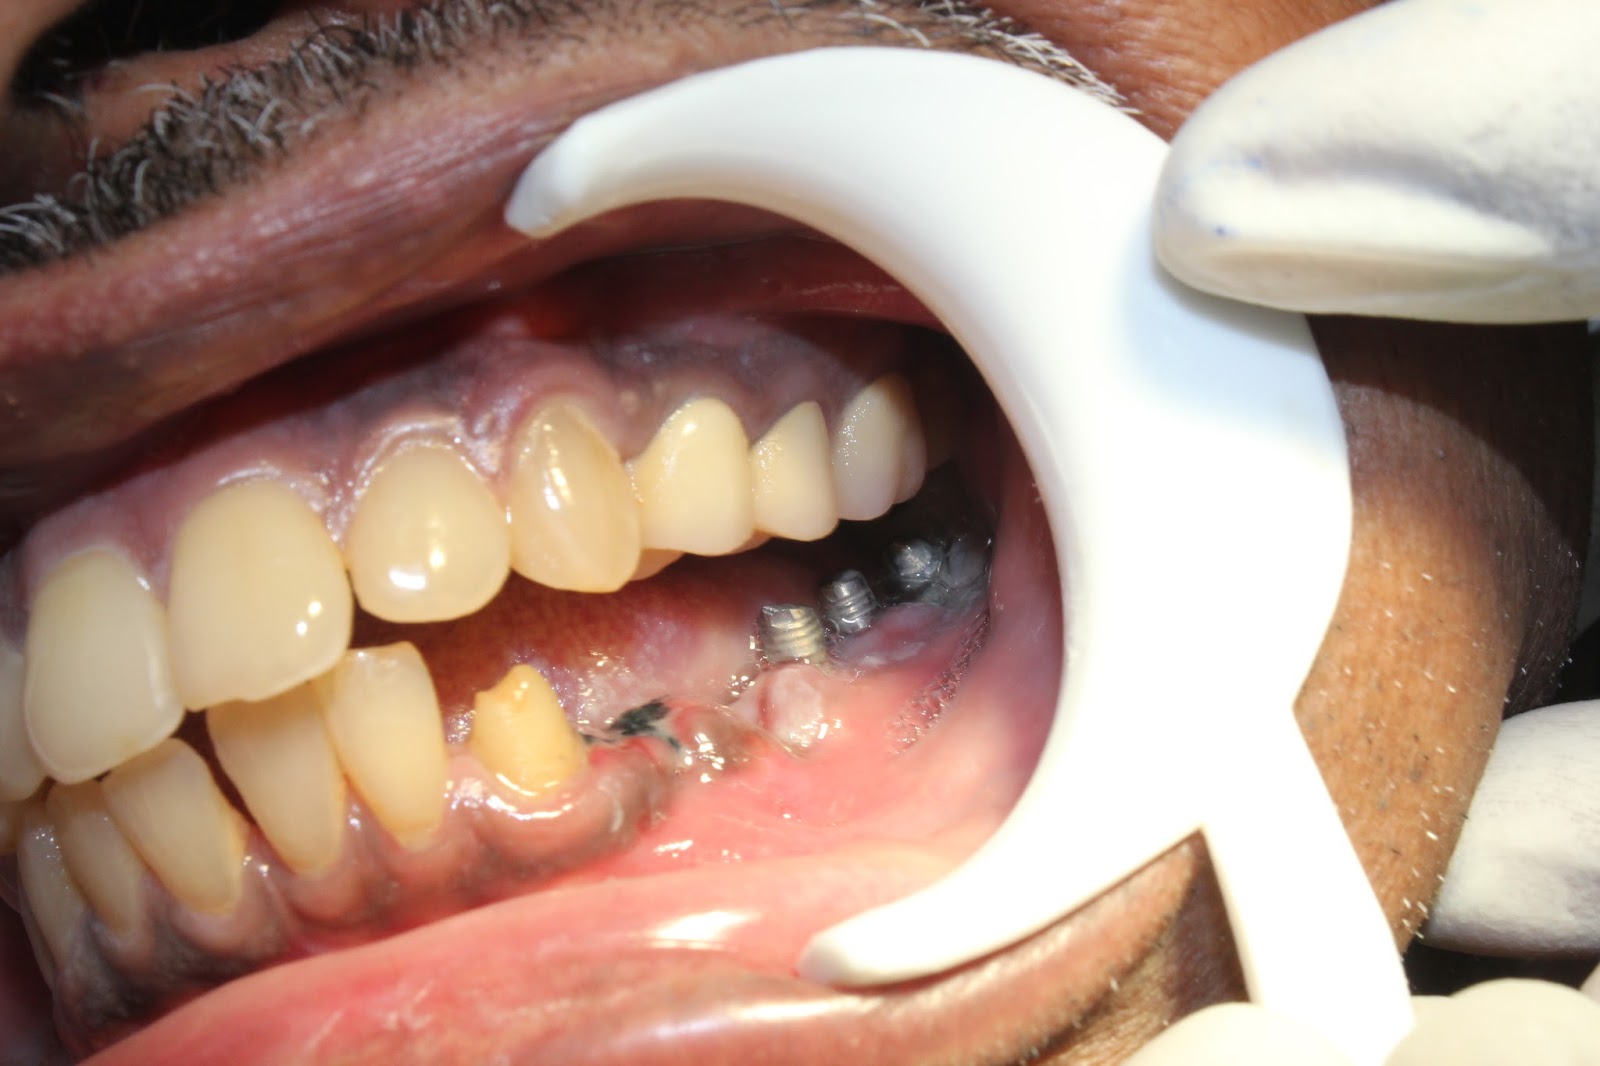

Replacement of 2 missing front teeth with dental implants and zirconia Zirconium Dental Replacement Dental implants are one of the best ways to replace missing teeth. dental implant surgery could be a proper restorative treatment for single, multiple, or completely missing teeth, regardless of age. Typically, implants are made of. It's a type of ceramic — or, in more specific terms, a. zirconia is a newer material for dental restorative treatments. . Zirconium Dental Replacement.

From bestlaserdentalclinic.blogspot.com